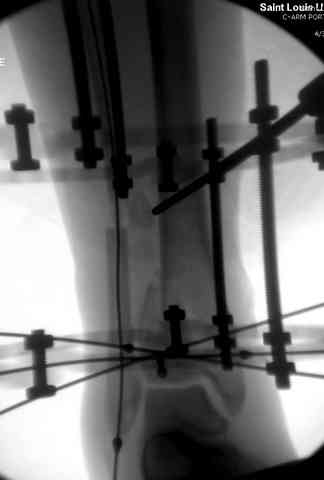

Здесь выставлена пара случаев перелома пилона, оба

случая леченные этапным наружным фиксатором.

Второй случай фиксирован аппаратом Илизарова.